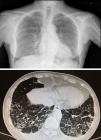

Chest X-ray and CT scan. Distortion of the pulmonary interstitium on the subpleural level of both bases, with thickening of the intralobular interstitium and interlobular septa, consistent with pulmonary fibrosis predominately on the posterior–basal subpleural level. Also bilateral basal cylindrical bronchiectasis.